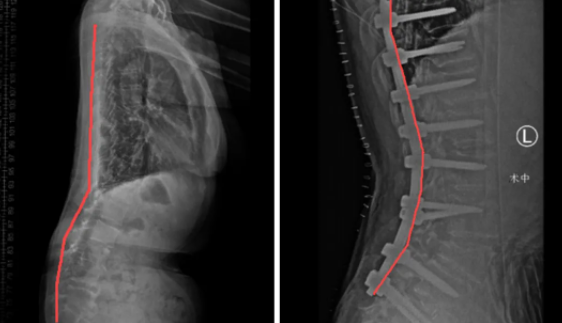

退变性脊柱侧弯术前(左)、术后(右)